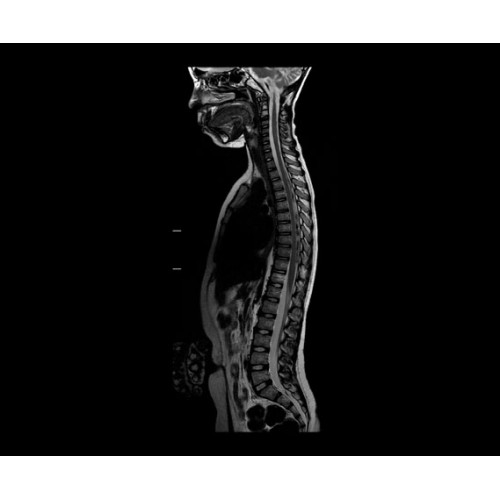

SIGNA PET/MR 3.0T — это гибридная система, в которой совмещаются две принципиально разные технологии — магнитно-резонансную томографию (МРТ) и позитронно-эмиссионную томографию (ПЭТ). Система отличающийся высокой чувствительностью и эффективностью и предназначена для диагностики в области онкологии, неврологии, кардио-васкулярных исследований, исследований воспалительных процессов.

Компания GE Healthcare представляет революционную, полностью интегрированную систему SIGNA PET/MR1, в которой сочетаются времяпролетная технология (TOF) и возможности напряженности магнитного поля 3.0 Тл. Мы поможем вам поднять исследования на более высокий уровень. SIGNA PET/MR позволяет достичь впечатляющей точности и скорости исследований, а благодаря новейшей технологии реконструкции Q.Clear2 качество изображений улучшается в два раза. Кроме того, в систему включен полный набор клинических приложений и гибких катушек для проведения любых видов исследования, открывая для вас возможности визуализации, о которых вы даже не догадывались.

Система SIGNA PET/MR предлагает впечатляющие клинические возможности и открывает доступ к наиболее полным пакетам программных приложений.